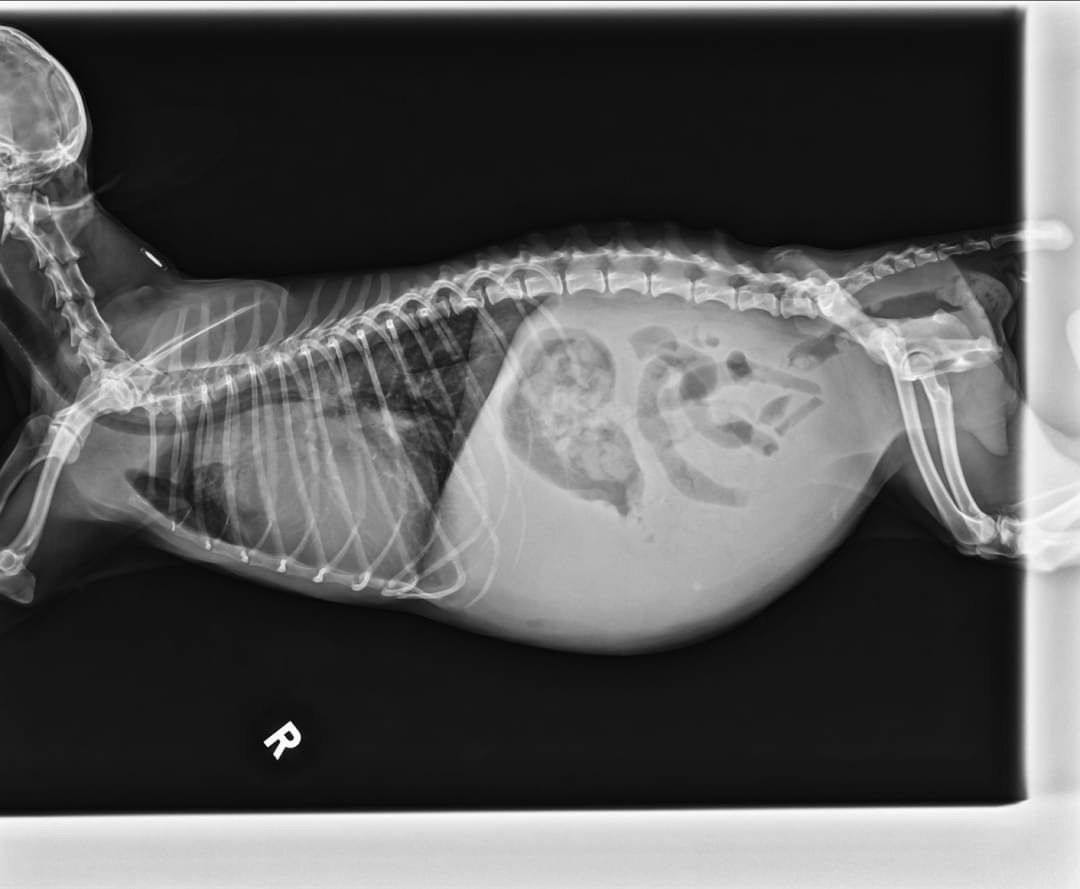

血液學檢查排除心絲蟲感染,並無明顯白血球上升跡象,X光影像學檢查下,可明顯發現動物心臟整體變大,主肺動脈幹明顯膨大,腹腔的輪廓度下降。